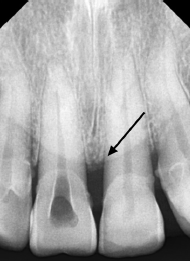

29. What is shown by the arrow?